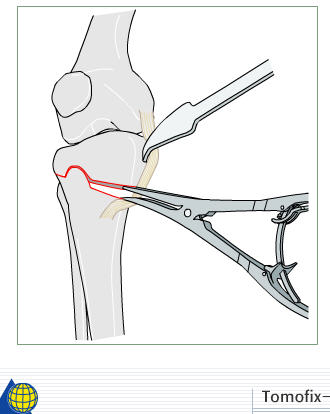

I prefer a medial opening wedge. Currently I prefer the tomofix system by synthes. Its instrumentation allows "dialing in" the correction nicely, and the fixed angle construct provides excellent stability. A few other companies have similar systems, Arthrex for example. Trying to hinge the correction on intact lateral cortex (1 cm.) is key to preserve stability.

Attached is a screen capture from the AO foundation website which has an excellent training module on performing an opening wedge HTO. It shows from preop planning to intra-op techniques. It is helpful even if you don't use their product to perform the procedure. Certainly it is not mandatory to use any osteotomy system to obtain and secure a well done osteotomy - im not sure what instrumentation you have access to.

4) if the correction is large( over 8 deg) or any cracks appear, or you put the limb axis in or beyond the neutral plane, so that the osteotomy is in tension rather than compression, then use a strong device( e.g. a Tomofix plate) rather than a minimal invasive device( e.g. a Pudu plate) - have both available if you're not sure, as the actual kit to do the osteotomy is a bit better on the Pudu set